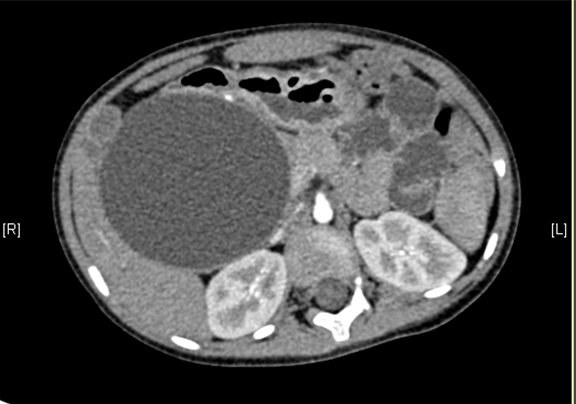

上腹部增强CT:考虑先天性胆管扩张症(胆总管明显)。

术前CT检查:

动脉期

静脉期

平衡期